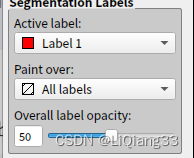

Active Label为激活的标签,表示当前使用的标柱类型,此时选择label 1为红色,说明使用红色进行标注paint Over为允许标注的范围,All labels允许对所有的标签进行标注,包括覆盖之前的标注;All visiable label是对所有可见的标签进行标注,如图,红色所在的位置则不能标注,